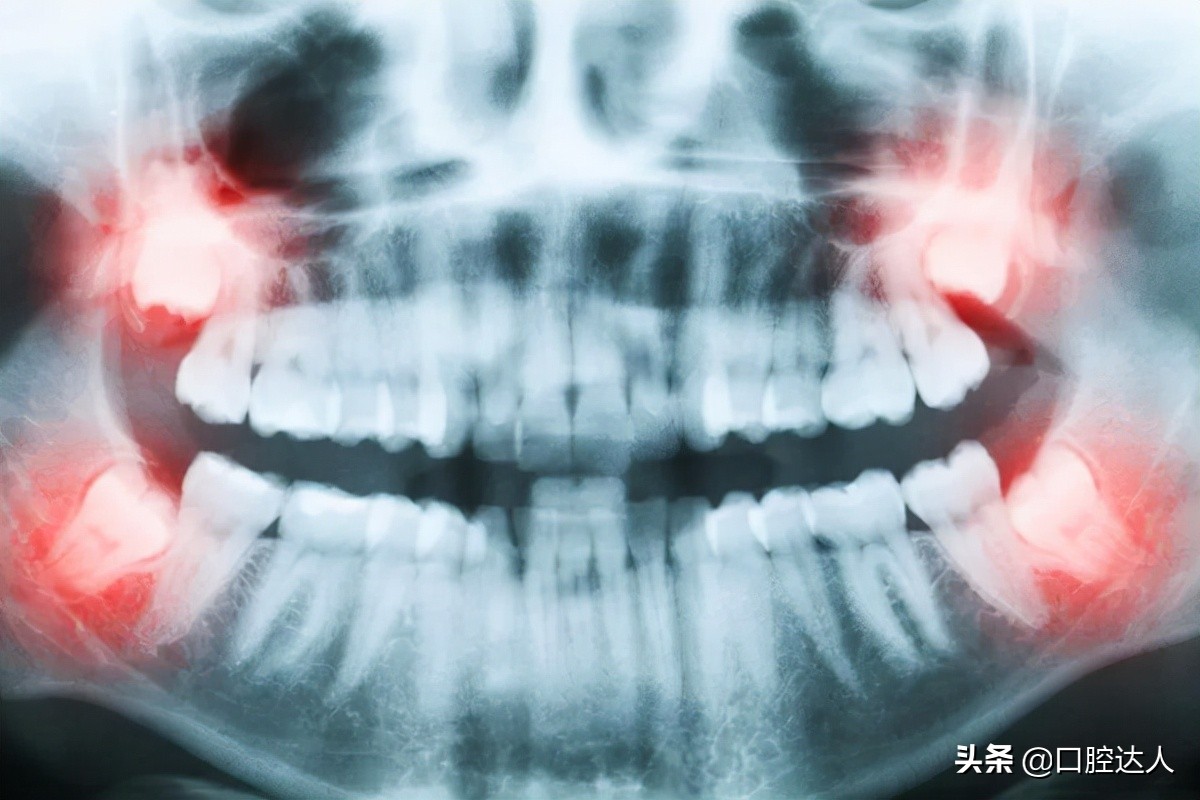

牙齿一旦龋坏,后期会导致牙髓组织发炎、水肿,水肿变大的牙髓使牙齿内部的压力变大,但被坚硬的牙齿紧紧包绕难以释放,就会引起剧烈的痛疼。

夜间人体在睡觉时平卧,头部的血运增加,发炎的牙髓压力加大,牙痛就会变得更加剧烈。白天有时被一些事情分散了注意力,阵发性痛疼尚可勉强忍受,但当夜深人静时会感觉疼痛难熬。

牙髓一旦发炎不可逆转,不能依靠吃药治愈。如果不及时治疗,发炎的牙髓会坏死形成急性根尖炎、慢性根尖炎、根尖囊肿。